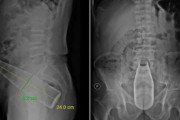

医者「ねぇ、なんで24センチのボトルを肛門から入れたの?」 患者「…察しろ」 → 出回ったレントゲン写真が衝撃すぎた…

はちま起稿

肛門に24センチのボトルを突き刺した男性 医師「なんで入れたの?」 男性「察してください」

暇つぶしニュース

肛門に24センチの瓶が入ってしまった男性 医師「なんで入れたの?」 男性「察してください」

痛いニュース(ノ∀`)